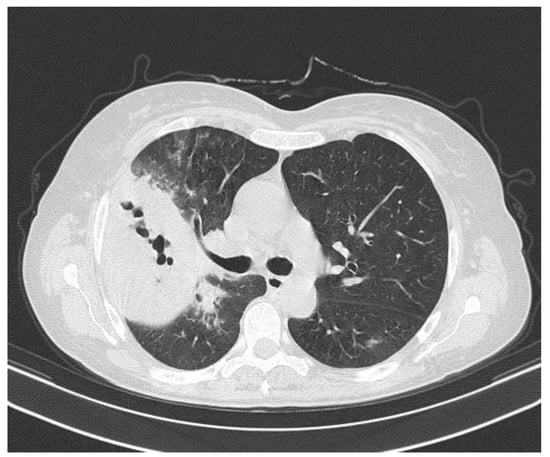

However, the patient showed no response after 2 days of therapy and developed hemoptysis. For this reason, the antibiotic treatment was shifted to i.v. piperacillin-tazobactam 4.5 g QID. A computed tomographic scan of the chest revealed an extensive area of consolidation with diffuse cavitation in the right upper lobe (Figure 2).

Figure 2.

Computed tomographic scan of the chest revealed extensive areas of pulmonary necrosis with diffuse cavitation in the right upper lobe.